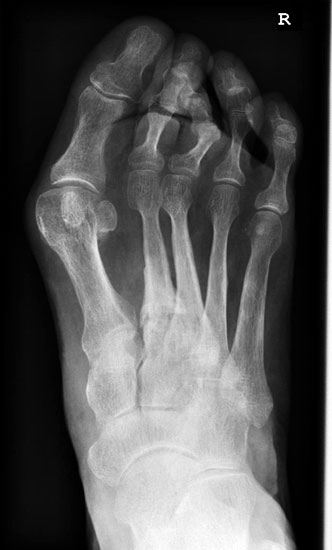

Entsprechend den beiden vorrangigen Manifestationsorten kann zwischen der Insertionstendopathie der Achillessehne am knöchernen Ansatzpunkt des Fersenbeines und der weiter proximal im freien Sehnenverlauf gelegenen, und daher „non-insertionalen“ oder „mid-portion“ Tendopathie unterschieden werden.

Hier befindet sich ca. 3-5 cm proximal des Tuber calcanei ein als „kritische Zone“ benannter Bezirk, der durch eine ungünstige arterielle Blutzufuhr gekennzeichnet ist (letzte Wiese). Hier finden sich häufig spindelförmige Schwellungen, die bei MRT-Diagnostik nicht selten partielle Nekrosen und Partialrupturen der Achillessehne aufweisen (Abb. 14).

Die distale Insertionstendinose der Achillessehne kann durch lokal entzündliche Prozesse/Mikrorupturen am Verankerungspunkt zur Ausbildung eines dorsalen knöchernen Fersenspornes führen. Dabei liegt die Prävalenz dorsaler Fersensporne bei achillären Insertionstendopathien bei etwa 6-8% (Lohrer 2002).

Unabhängig davon können insbesondere chronische Insertionstendinosen der Achillessehne von Partialrupturen (Abb. 15) und erosiven Läsionen des dorsalen Fersenbeines begleitet sein.

Insbesondere bei größeren Partialrupturen (Abb. 14) sollten operative Verfahren erörtert werden. Kleinere Partialrupturen sind der ESWT gut zugänglich, wie die beiden nachfolgenden Beispiele zeigen: